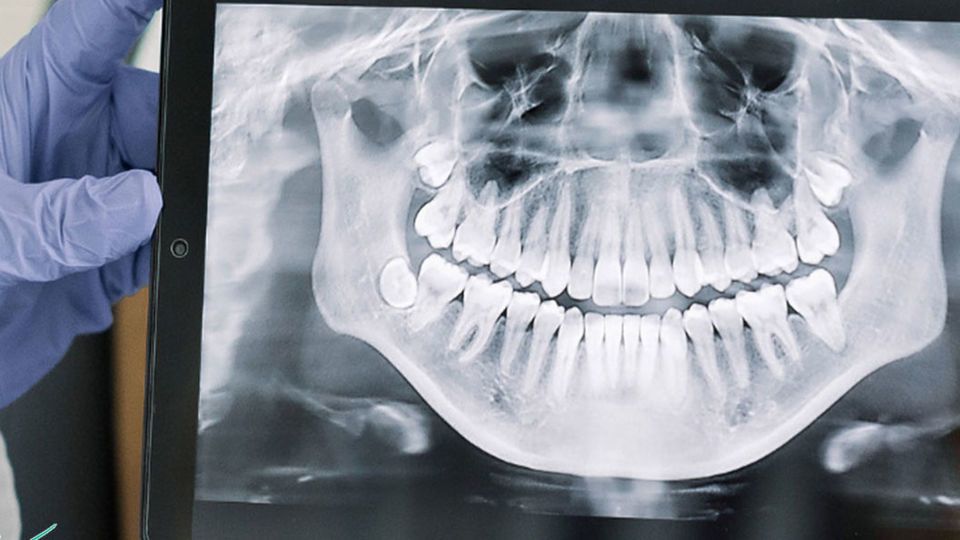

در روزهای اخیر شاهد انتشار آمارهای جدید درباره یک مشکل قدیمی در حوزه بهداشت و درمان کشورمان بوده‌ایم.  "محمد رضا ظفرقندی" وزیر بهداشت، درمان و آموزش پزشکی کشورمان در موضع گیری گفته است که" ۵۵ درصد از سالمندان بالای ۶۵ سال کشورمان کاملا فاقد دندان هستند. در حالی که این شاخص در دنیا ۲۵ تا ۳۰ درصد است".

وی تاکید کرده که " ۱۸ درصد از مردم هیچگونه روش بهداشتی در مراقبت از دندان را رعایت نمی کنند و این رقم در دهک های پایین اقتصادی به ۵۰ درصد می رسد که به توجه جدی نیاز دارد". ورای این ها، "زهرا قربانی"، سرپرست اداره سلامت دهان و دندان وزارت بهداشت هم در موضع گیری تاکید کرده که "کودکان ۶ ساله ایرانی به طور متوسط ۵ دندان شیری پوسیده دارند و در کودمان ۱۲ ساله نیز حدود ۲ دندان دائمی پوسیده مشاهده می شود".

در سایت های خبری مختلف شاهد بوده ایم که خبری مبنی بر وجود ۲۵۰ میلیون دندان پوسیده در دهان مردم ایران منتشر شده است. بر اساس آمارهایی از این دست، هر ایرانیِ بین ۳۰ تا ۴۰ سال، بیش از ۶ دندان پوسیده دارد. مجموع این مسائل نشان می دهند که کشورمان در حوزه بهداشت دهان و دندان، با چالش های جدی دست به گریبان است.